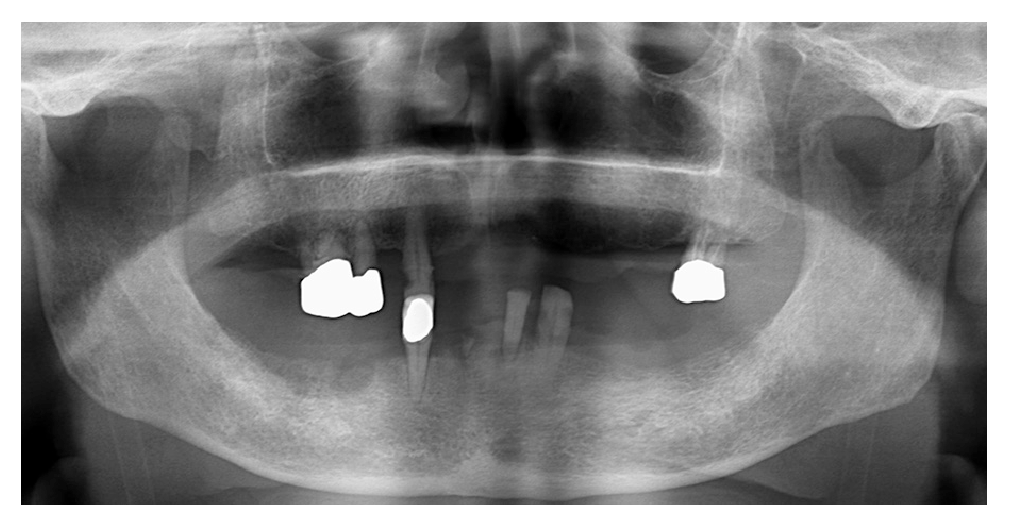

パノラマX線所見:病変に関連する顎骨内病変はない(図2)。